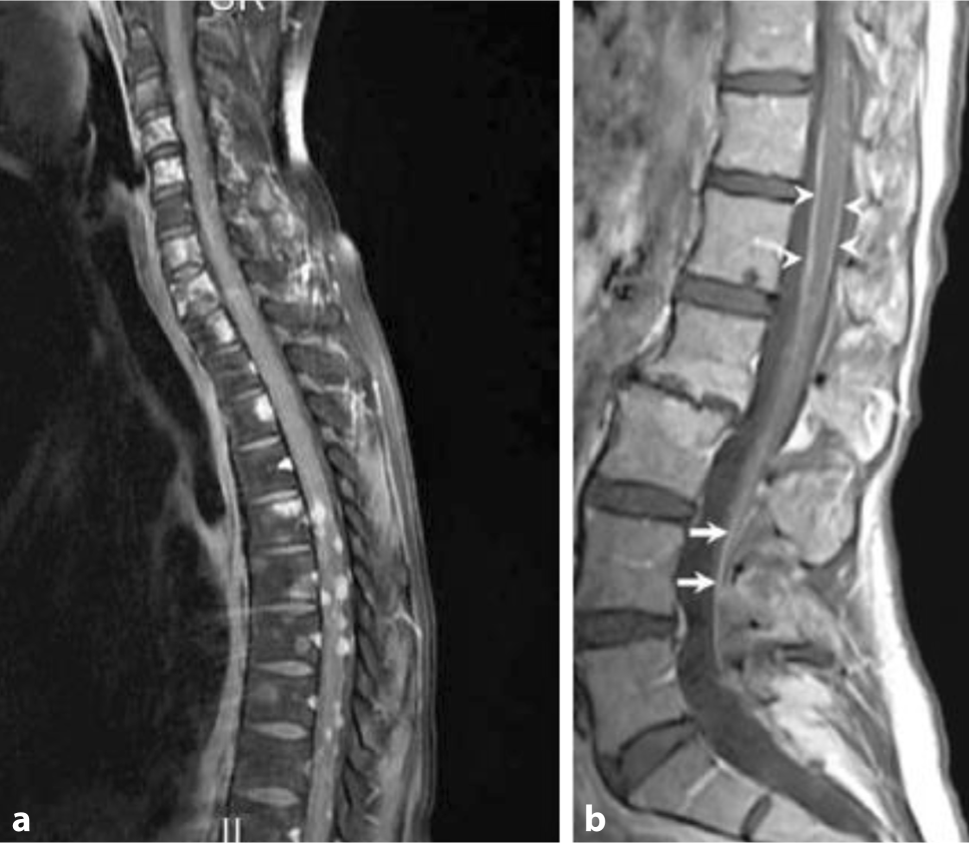

A distinction is made between nodular tumour growth, adherent to the meninges, linear spread and freely floating tumour cells or a combination of these manifestations (Fig. 1).

Nodular (a) and linear (b) leptomeningeal tumour growth

Therapeutic consequences result from these different growth patterns, as assessed by imaging and CSF cytology. In case of extensive nodular and symptomatic manifestation, local radiotherapy (RT) is recommended, whereas 1–2 mm layers or freely circulating tumour cells are probably more accessible to intrathecal (i.th.) and systemic therapy. We would rather not recommend i.th. therapy for nodular disease without a positive CSF cytology on repeated sampling through lumbar puncture. RT may also be an option for the treatment of CSF flow blocks.